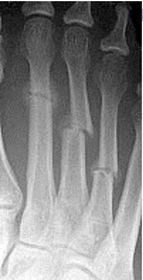

| What disease is this? | Atrophic neuroarthropathy |

| What disease is this? | Atrophic forefoot neuropathy (diabetic osteolysis) |